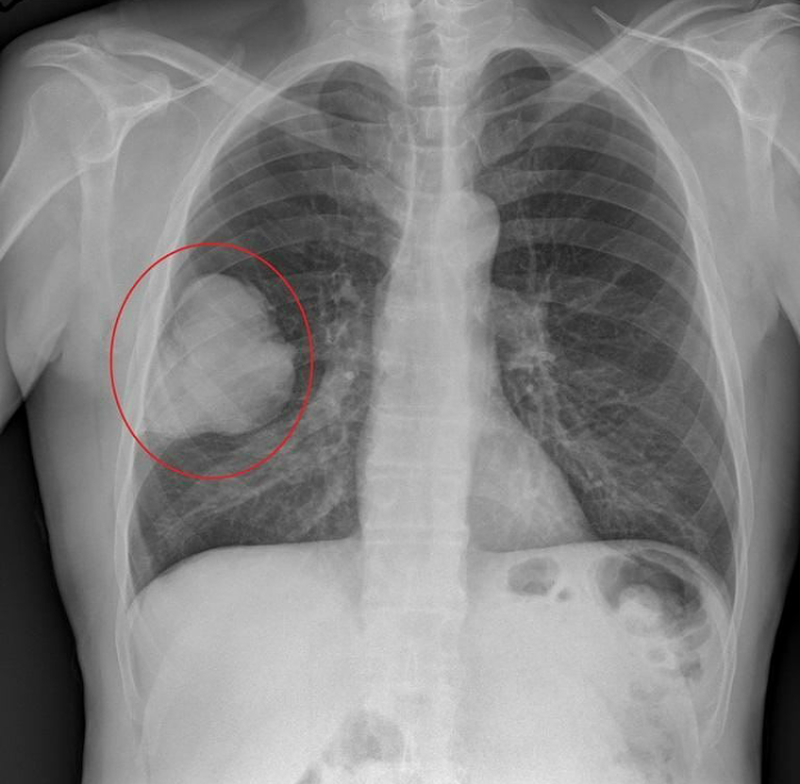

Lung cancer typically doesn't cause signs and symptoms in its earliest stages.Signs and symptoms of lung cancer typically occur only when the disease is advanced. Signs and symptoms of lung cancer may include: A new cough that doesn't go away Coughing up blood, even a small amount Shortness of breath Chest pain Hoarseness Losing weight without trying Bone pain Headache